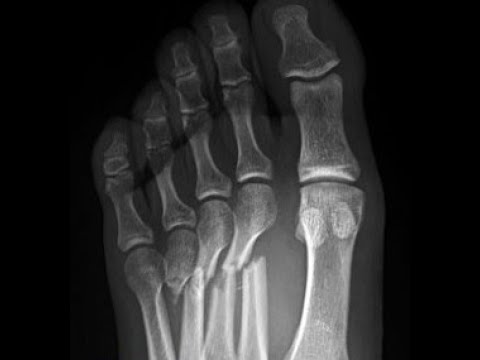

Перелом джонса без смещения 115 фотографий